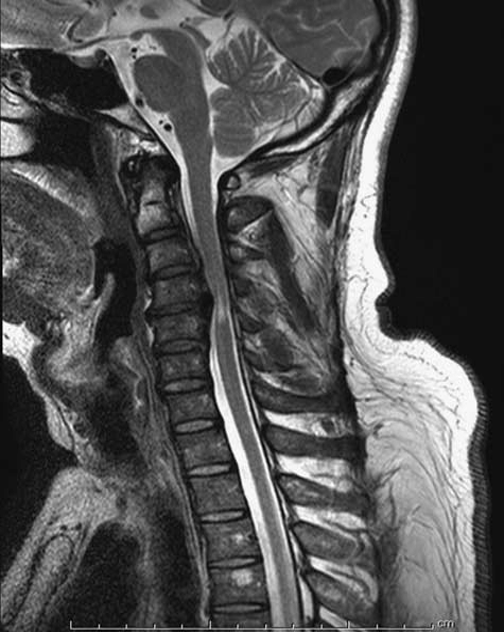

• Degenerative osteophytes compress the spinal cord.

• Reduced AP diameter of spinal canal.

• Cord flattening seen.

• T2 hyperintensity indicates myelomalacia.

• Most common cause of compressive myelopathy.

A sagittal T2-weighted magnetic resonance imaging of cervical spondylotic myelopathy patient shows the change of spinal cord signal intensity.